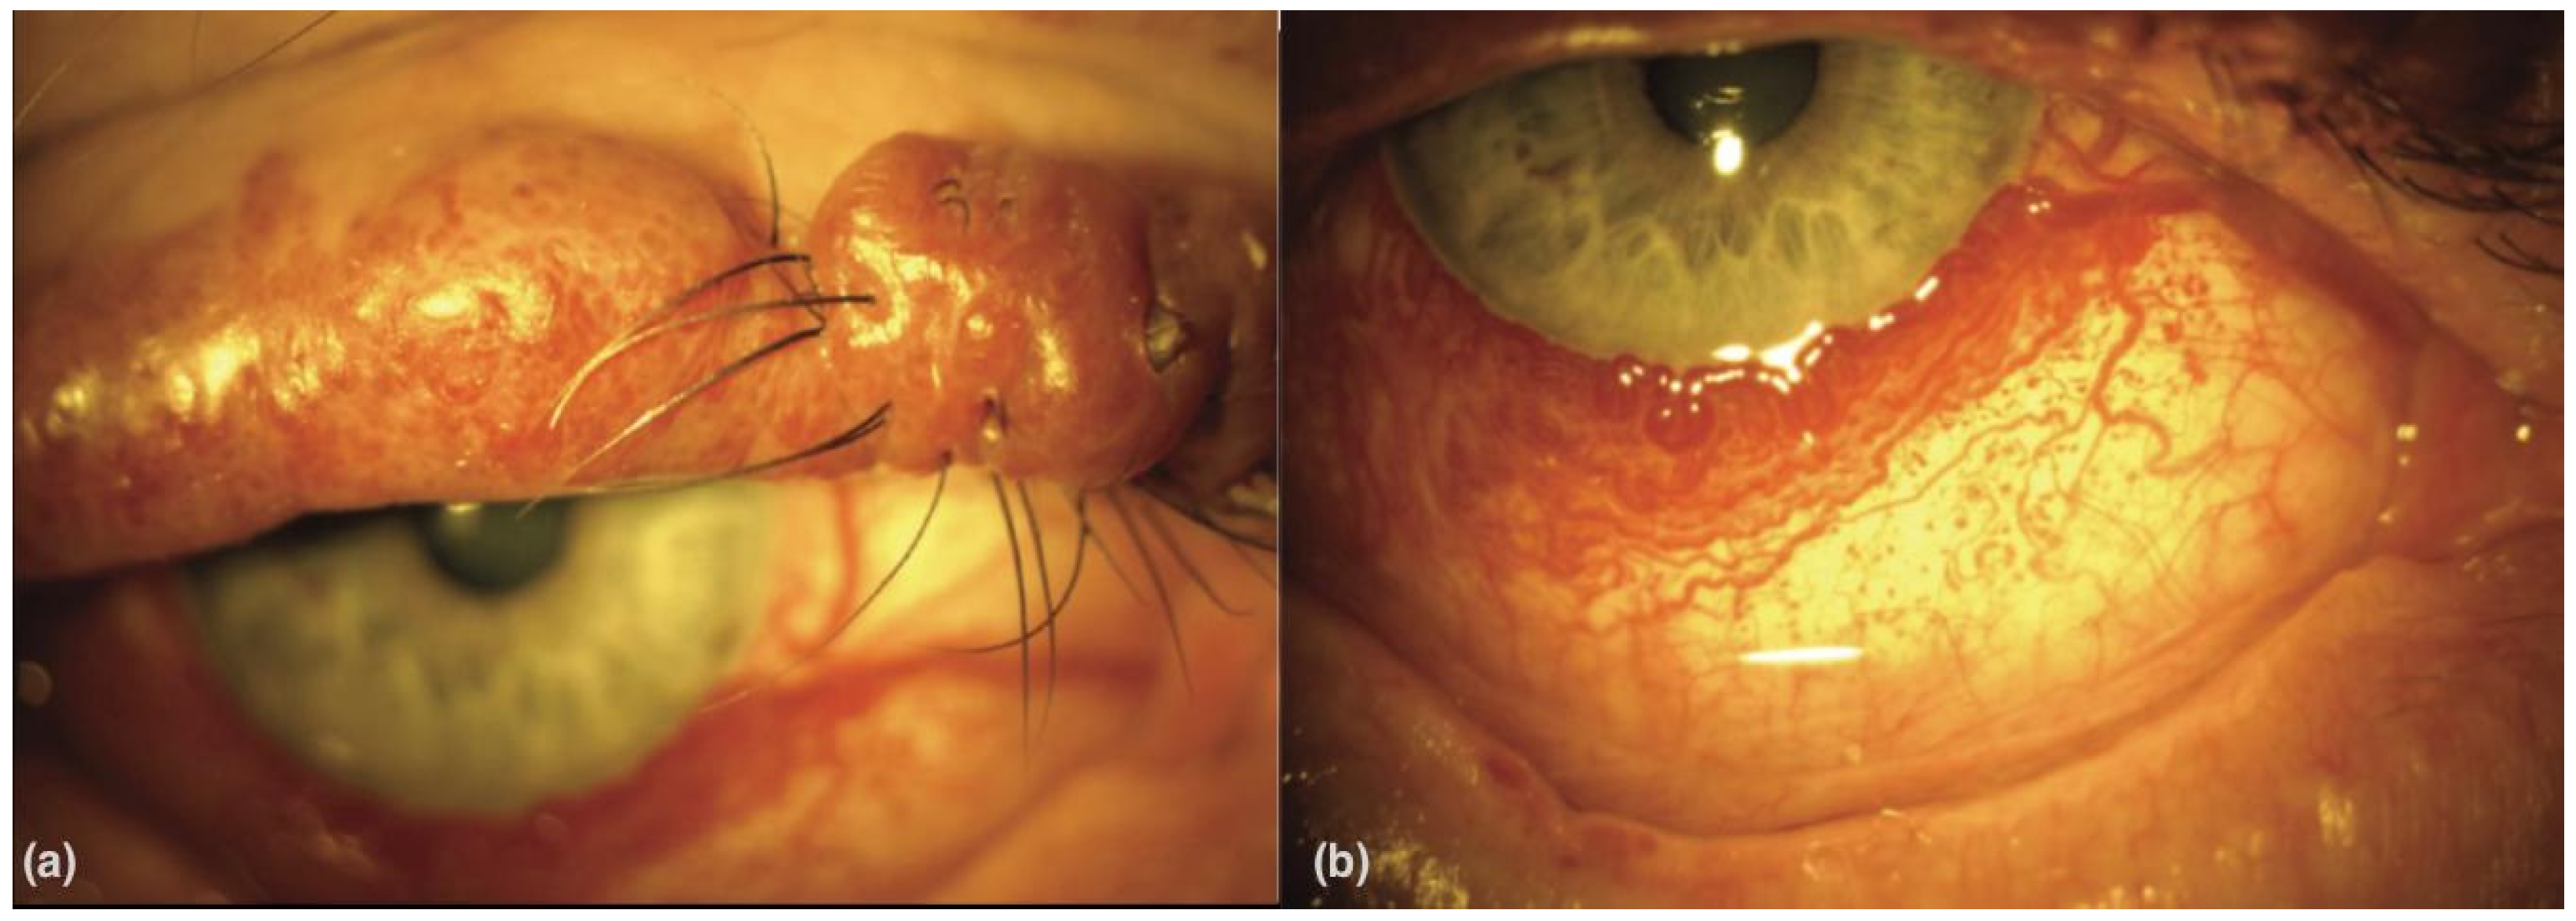

2.1. Histopathological Findings and Clinical Characteristics of Choroidal Hemangiomas in Sturge-Weber Disease

2.2. Fundus Photography